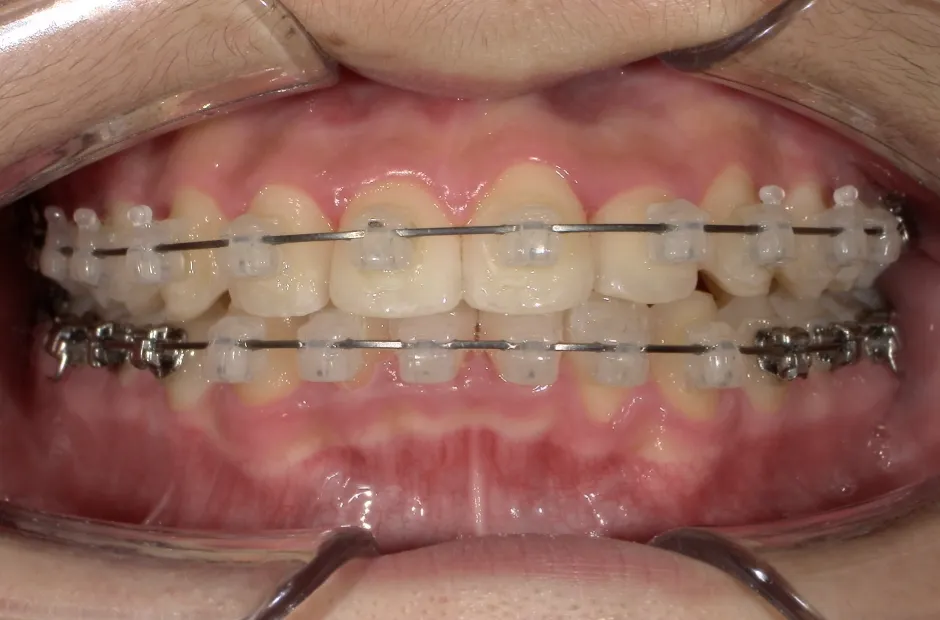

ブラケット矯正

前歯部反対咬合

| 診断名・主訴 | 前歯部反対咬合 |

|---|---|

| 年齢・性別 | 14歳・男性 |

| 治療期間・回数 | 1年2か月 |

| 治療に用いた主な装置 | ブラケット矯正 |

| 抜歯部位 | なし |

| 治療費 | 60万円(税抜) |

| リスク・副作用 | 装置による違和感・疼痛・歯肉退縮・歯根吸収・虫歯のリスクなど |

治療前

治療中

治療後